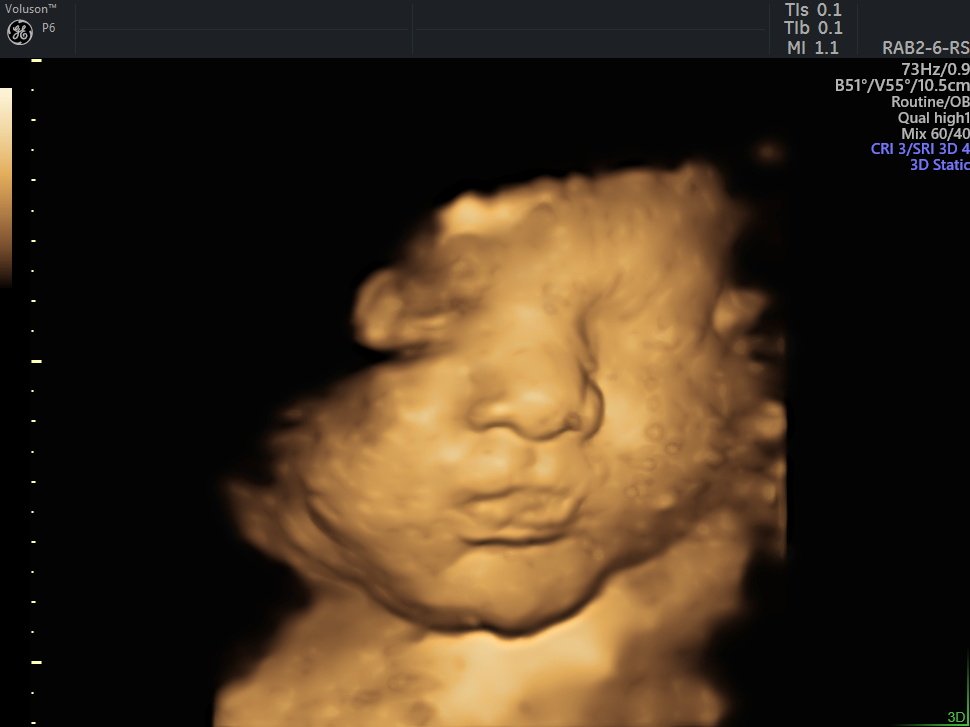

4 Boyutlu (Renkli) Ultrason ve Doppler Ultrasonografi

4 D Ultrasonografi